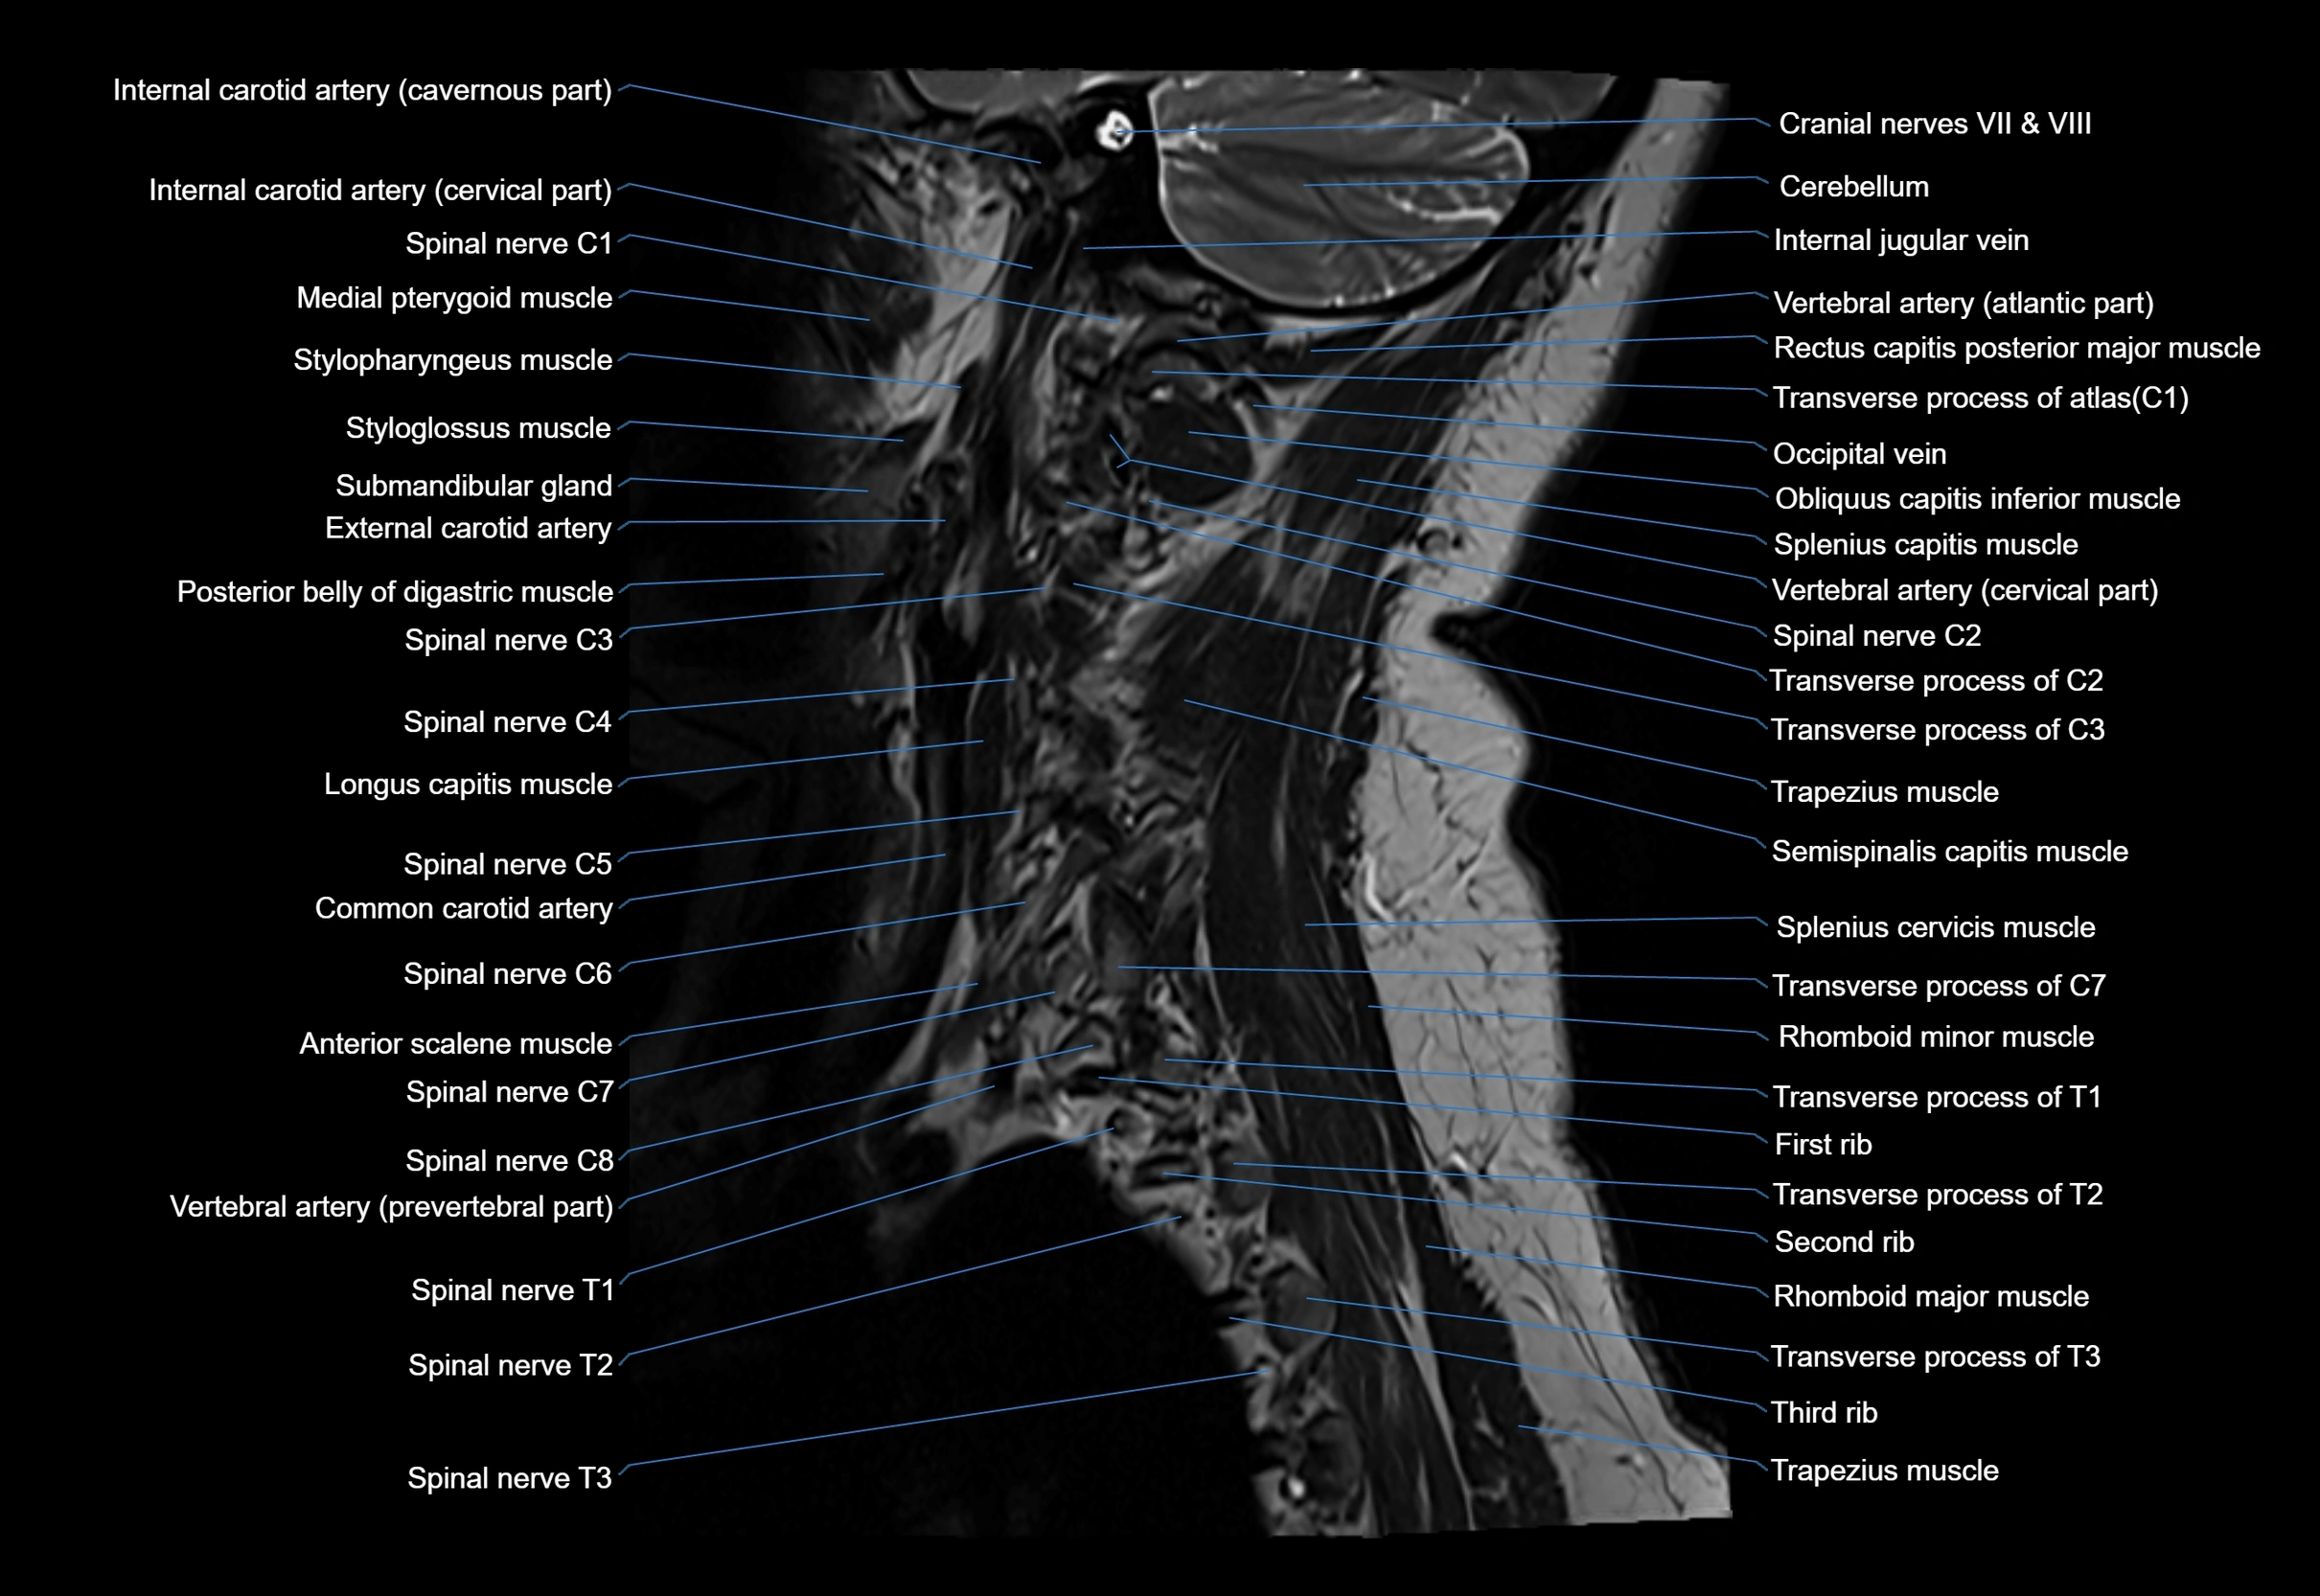

MRI appearance

T1-weighted images:

• Annular epiphysis: Low signal cortical rim at the vertebral margin

• Adjacent marrow: Intermediate-to-high signal in the vertebral body

• Disc interface: Clear delineation between bone and annulus

T2-weighted images:

• Annular epiphysis: Low signal intensity line

• Endplate cartilage (in younger patients): Intermediate signal

• Intervertebral disc: High signal nucleus pulposus

STIR:

• Annular epiphysis: Low signal cortical rim

• Adjacent marrow: Suppressed fat signal with preserved bony outline

• Utility: Highlights marrow and endplate interface in developing spine

MRI image

image